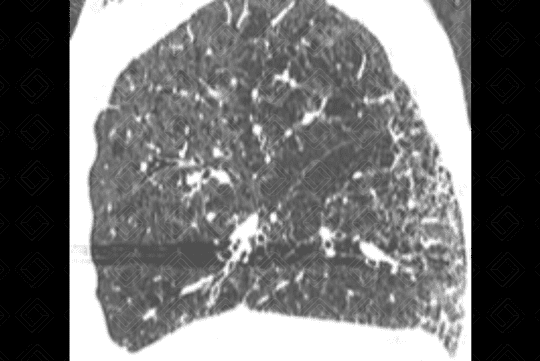

Texto alternativo para a imagem Figura 3. Créditos: Dra. Elazir Mota - Rio de Janeiro/RJ

Descrição das figuras 3, 4, 5 e 6: Tomografia computadorizada do tórax seguida de aquisições coronais, sagitais e axiais mostrando as extensas áreas de enfisema centrolobular dispersas pelo parênquima pulmonar (setas vermelhas).

• Tomografia computadorizada do tórax: Este método é mais sensível e específico que a radiografia de tórax na avaliação do enfisema. Tem sido empregado para detectar, quantificar e caracterizar a doença. A tomografia é capaz de diferenciar os vários tipos de enfisema, que pode ser classificado, de acordo com a região do ácino acometida, em proximal (centrolobular ou centroacinar - figuras 3, 4, 5, 6, 9, 10 e 11 ), distal (parasseptal - figuras 7, 8, 9, 10 e 11 ) ou todo ácino (panacinar ou panlobular).